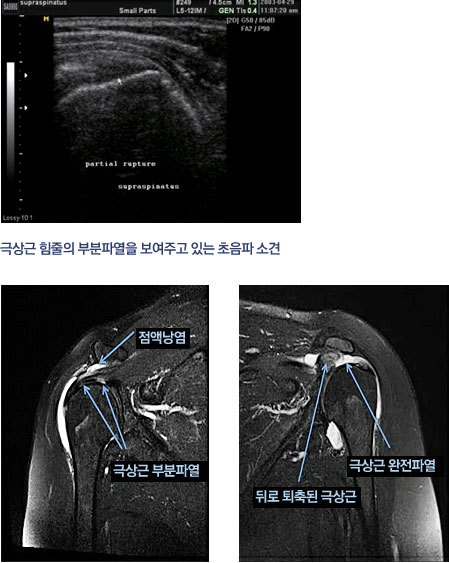

Q=어머니는 오랫동안 어깨를 앓고 있었지만, 얼마 전부터 잠자리에서도 어깨 통증에 시달리고 있습니다. 팔도 거두는 것이 큰일이라고 합니다. A=흔히 있는 어깨의 질환으로 충돌 증후군(회전 근개 손상)오십견(유착성 관절 피막염), 석회화 건염, 관절 와진 파열, 근막 통증 증후군 등이 있고 외에도 목과 어깨의 다양한 부위의 신경 압박으로 어깨의 통증이 있습니다. 많은 환자들이 이렇게 말하고 있습니다. “여러 병원·의원에서 뢴트겐(X선)을 찍고 이상이 없는 주사를 맞아 물리 치료를 했지만 별로 효과가 없어 그 때만 증세가 더 심해지는 것 같아요.”X선에서는 뼈 이외의 무수한 구조물을 볼 수 없습니다. 골절에 의한 어깨 통증 외에 엑스 레이로 보이는 어깨 통증의 원인은 골암와 석회화 건염 뿐입니다. 그러므로 외상이 없을 때는 X선 검사는 필요 없다고 생각합니다. 많은 분들이 장기간 충돌 증후군의 치열한 인대 손상을 주사와 물리 치료에만 의존했으나 수술 시기를 놓쳐서 심한 관절염으로 팔을 쓰지 못한다 아쉬운 경우를 자주 봅니다. 어깨의 회전통과 활막이 어깨 관절을 안정시키는 유일한 구조물입니다. 그래서, 인대 손상과 어깨의 회전통이 심한 위축이 오면 어깨 관절이 불안정해지면서 장기적으로 치열한 관절염에 진행되고 팔을 못쓰게 될 뿐 아니라, 아파서 잘 수 없게 됩니다. 진찰시에 충돌 증후군이 의심스러우면 꼭 자기 공명 영상(MRI)검사를 해야 합니다. MRI영상으로 힘줄 손상 정도로 근육의 퇴화 정도를 보며 수술 여부를 정합니다. 그래서 미국의 상당수 주에서 MRI검사 없이는 관절경 수술을 금지하고 있습니다. -영상 의학과 의원(소죠은데 원장)-

Q=어머니는 오랫동안 어깨를 다치셨지만, 얼마 전부터는 잠자리에서도 어깨 통증으로 고생하고 계십니다. 팔도 올리기 힘들대요. A=흔히 흔한 어깨질환으로 충돌증후군(회전근개손상), 오십견(유착성관절막염), 석회화건염, 관절와순파열, 근막통증후군 등이 있으며 이외에도 경추나 어깨 여러 부위의 신경압박에 의한 어깨통증이 있습니다. 많은 환자들이 이렇게 말합니다. 여러 병의원에서 엑스레이(X-ray)를 찍고 이상이 없어 주사를 맞고 물리치료를 했는데 별 효과가 없고 그때만 증상이 더 심해지는 것 같아요. 엑스레이에서는 뼈 이외의 무수한 구조물을 볼 수 없습니다. 골절에 의한 견통 외에도 엑스레이에서 볼 수 있는 견통의 원인은 골암과 석회화 건염뿐입니다. 그렇기 때문에 외상이 없을 때는 엑스레이 검사는 필요 없다고 생각합니다. 많은 분들이 장기간 충돌증후군으로 인한 극심한 인대 손상을 주사와 물리치료에만 의존하다가 수술 시기를 놓쳐 심한 관절염으로 팔을 사용할 수 없게 되는 안타까운 경우를 자주 봅니다. 어깨 회전근과 활막이 견관절을 안정시키는 유일한 구조물입니다. 따라서 인대 손상과 어깨 회전근의 심한 위축이 오게 되면 견관절이 불안정해지고 장기적으로 심한 관절염으로 진행되어 팔을 사용하지 못하게 될 뿐만 아니라 아프고 잠을 잘 수 없게 됩니다. 진찰 시 충돌증후군이 의심되면 반드시 자기공명영상장치(MRI) 검사를 해야 합니다. MRI 영상에서 힘줄 손상 정도와 근육 퇴화 정도를 보고 수술 여부를 결정합니다. 따라서 미국의 많은 주에서 MRI 검사 없이는 관절경이나 수술을 금지하고 있습니다. – 영상의학과의원(서정대원장)-